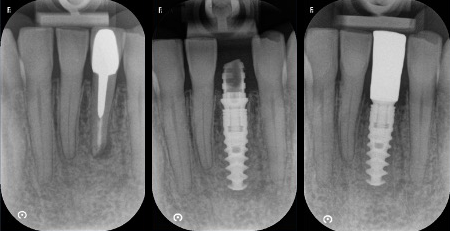

Cas esthétique d'implant unitaire

Mise en charge immédiate

Avec un implant unitaire et la mise en charge immédiate dans les zones esthétiques (quand c’est possible et selon le cas observé), la phase de cicatrisation, normalement de quelques semaines, se déroule avec une dent provisoire fixe (couronne provisoire vissée) qui permet d’éviter l’installation d’une prothèse provisoire amovible (dentier). Cela épargne aux patients de subir une intervention supplémentaire et il s’agit aujourd’hui d’une procédure standardisée, très confortable et très appréciée par les patients. C’est uniquement dans les cas exceptionnels, comme par exemple en cas d’infections aiguës, qu’il est préférable d’extraire d’abord la dent délabrée et de poser l’implant seulement lorsque l’inflammation est résolue.